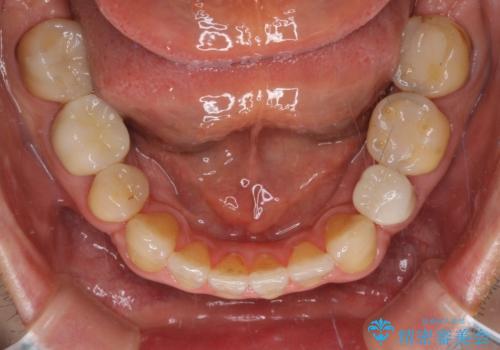

- むし歯による奥歯の痛みを気にして来院された患者様です。

神経にまでむし歯の及んでいる歯や、既に根管治療がされている歯に痛みがあったため、まずは根管治療を行うこととしました。

その後、以前行った抜歯矯正の後戻りをインビザライン・ライトにより改善し、むし歯や銀歯はオールセラミッククラウンにて補綴治療することとしました。